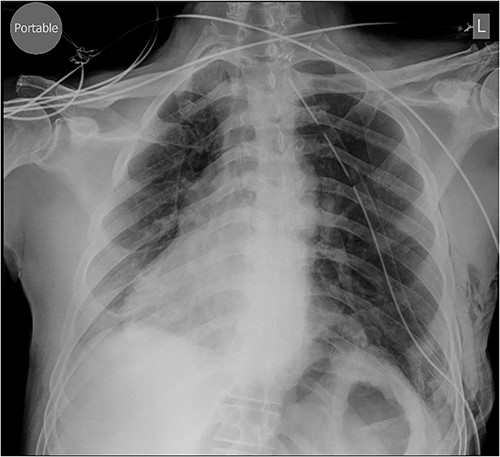

Repair was performed via Video-Assisted Thoracoscopic Surgery with an 8 cm access incision and a 5 mm camera port. The central lax portion of the diaphragm was staple resected using an Ethicon stapler followed by plication of remaining redundant diaphragmatic tissue using 2/0 polypropylene running suture. Postoperative chest X-ray showed acceptable descent of the left hemidiaphragm (Fig. 2). Hospital length of stay was 7 days. Postoperative course was complicated by subcutaneous hemorrhage, and development of a left pleural effusion post discharge drained 2 weeks postoperatively by thoracentesis. He also developed severe hiccoughs, settling on a course of esomeprazole. Histology of the 13 × 5 cm resected portion of diaphragm was consistent with eventration. The patient endorsed complete resolution of symptoms at 1 year post-repair and was seen at 2 years post-repair with no issues (Fig. 3).